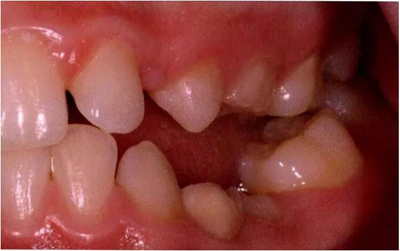

圖1:輕度下沉的臨床像

圖8展示了一張5歲孩子右下第二乳磨牙嚴(yán)重下沉的口內(nèi)像。臨床檢查可見右下第一乳磨牙遠(yuǎn)中傾斜,朝向下沉乳牙。X線片檢查顯示所有恒牙胚都存在(圖9)。無論是臨床還是影像學(xué),都可檢查到有齲齒的存在。鑒于這顆下沉乳牙在年齡較小時(shí)就已經(jīng)非常嚴(yán)重,同時(shí)還患有齲病,因此決定予以拔除。后期在放置間隙保持器的同時(shí)還應(yīng)持續(xù)觀察監(jiān)測(cè)右下第一恒磨牙和第二前磨牙的萌出情況。

圖8:一名五歲患兒右側(cè)下頜第二乳磨牙嚴(yán)重下沉臨床像